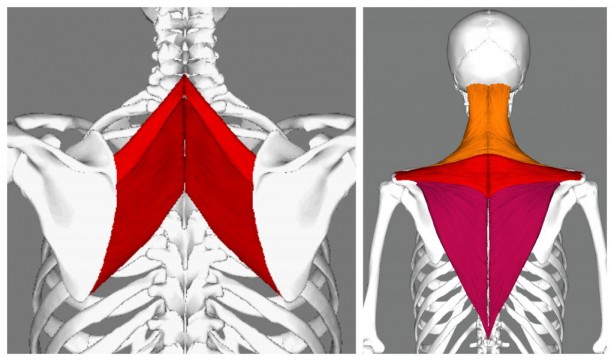

Duruş bozukluklarının fiziksel ve ruhsal olarak birçok soruna yol açabileceğini belirten Fiziksel Tıp ve Rehabilitasyon Uzmanı Dr. Esin Selimoğlu, yanlış duruş pozisyonlarının, boy kısalmasına dahi neden olabileceğini söyledi.